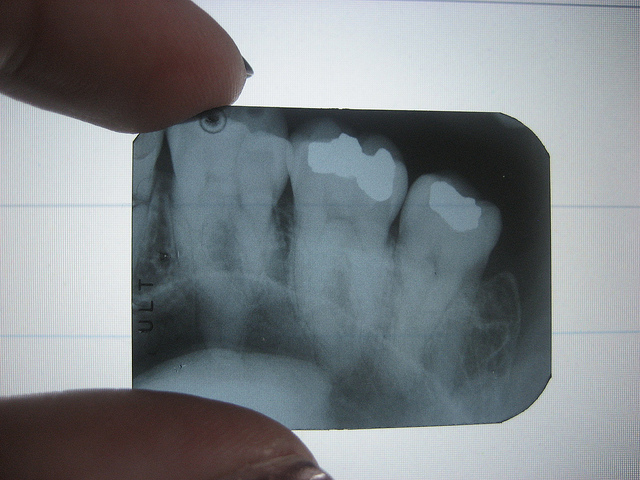

- Bitewings – a small X-ray view that shows the upper and lower back teeth simultaneously, where the patient bites down on a small holder filled with the X-ray film. Bitewings are frequently used during regular checkups to look for cavities.

- Full-mouth – a series of about 14-21 X-ray films that are used to view the entire mouth for dental problems, usually performed during a person’s first visit to the dentist.

- Panoramic – a single X-ray that shows a broad view of the entire mouth to provide information about the teeth, jawbones, sinuses, and other tissues of the head and neck. Panoramic X-rays are taken occasionally, often to evaluate wisdom teeth, using a machine that moves around the patient’s head.